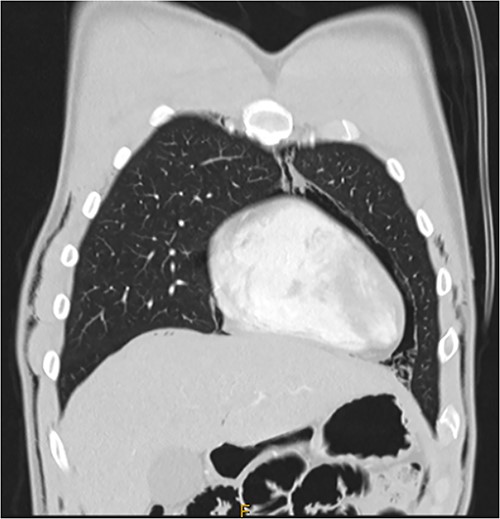

Following extubation, bilateral chest wall subcutaneous emphysema was noted extending to the neck. He also complained of central chest discomfort, without respiratory distress, oxygen desaturation or airway obstruction. Chest X-ray (CXR) revealed pneumomediastinum and surgical emphysema in the lateral chest walls bilaterally. Computed tomography (CT) of the chest, abdomen and pelvis demonstrated large volume subcutaneous emphysema bilaterally in the scrotum, abdominal and chest walls extending to the neck (see Figs 2–5). Gas was noted between the abdominal muscle layers, extraperitoneal and retroperitoneal spaces without pneumoperitoneum (see Figs 5–6). Moderate pneumomediastinum was prominent within the superior and antero-inferior mediastinum without evidence of tracheal or oesophageal injury and an associated small left pneumothorax was noted (see Figs 1–3).

CT chest coronal, pneumomediastinum and bilateral subcutaneous emphysema.